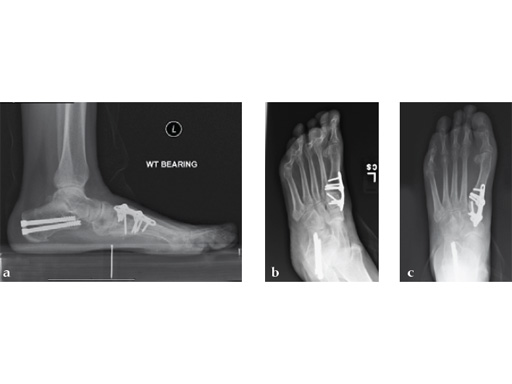

Case 5: First TMT, straight fusion and TMT fusion plates

A 46-year-old obese woman with coronary artery disease had sustained a Lisfranc injury while performing an exercise program. She was unable to weight bear and used an electric scooter.

In an effort to restore her ability to exercise and taking into consideration her body weight and upper extremity weakness, a decision was made to use the variable angle locking compression plate. These postoperative x-rays were obtained at 3 months, one month after beginning weight bearing. The patients pain was reduced and she was able to resume a progressive exercise program after 4 months following surgery.

Case provided by Michael Castro, Scottsdale, Arizona